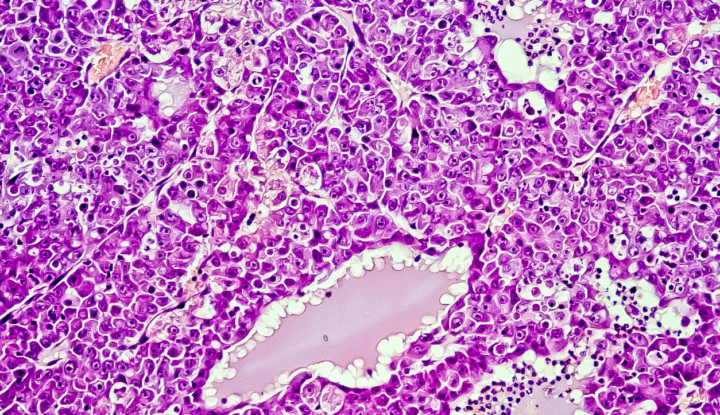

A MuTaTo, vagyis multi-target toxin névre keresztelt fejlesztés a fág-display eljárások körébe tartozó technika segítségével, peptidekkel támadja a rákos sejteket. A betegek számára a biopsziás vizsgálatok eremdényei alapján személyre szabott koktélt tudnak előállítani.

Dr. Ilan Morad, a vállalat vezetője ígéretes egérkísérleteikről és in vitro kísérletekről számolt be: ezek során a terápia az egészséges sejteket nem támadta meg, de a daganatos szöveteket sikeresen eltűntették. A kutató szerint a kísérleteik hamarosan klinikai fázisba érnek.